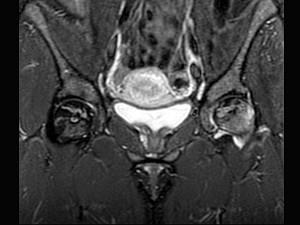

问题 女,34岁,双侧髋部疼痛,结合图像,最可能的诊断是 ( )

选项 A、股骨头缺血坏死 B、痛风 C、类风湿关节炎 D、髋关节退行性变 E、未见异常

答案 A